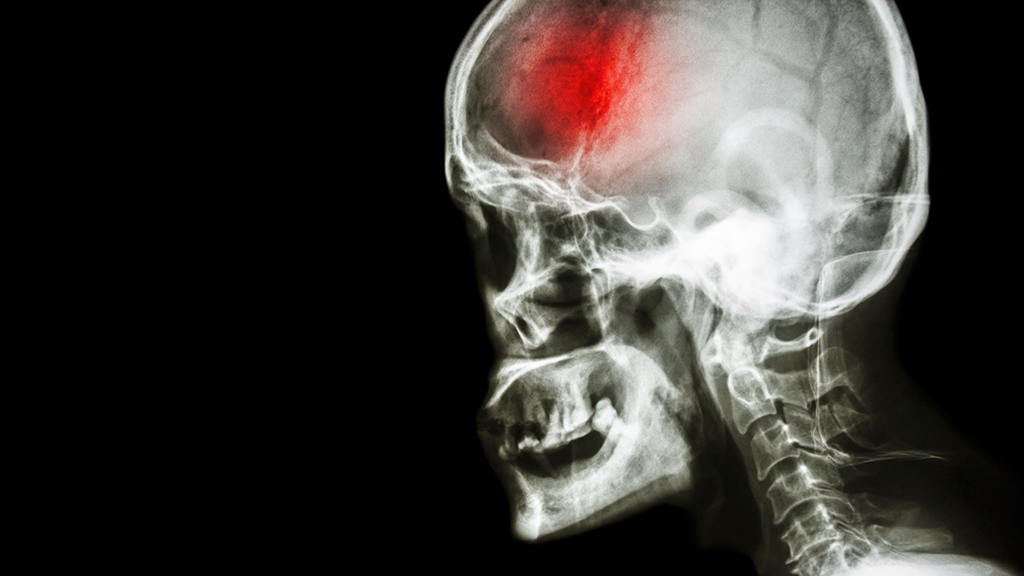

This directed case study tells the story of a middle-aged man with hypertension and hyperlipidemia who experiences an ischemic cerebrovascular accident. The case provides an opportunity for students to integrate the brain's functional anatomy related to control of speech and body movement, and to examine how disruption of the brain's blood supply can have systemic effects. Students learn the anatomy of the brain's blood supply and explore the neural integration of upper motor neurons in the quadriceps reflex. Group discussion is used to teach the post-stroke symptoms of hemiparesis (primarily in the lower extremity), dysphasia, and alien hand syndrome. The case was originally developed for upper-level undergraduate biology majors following their coursework in anatomy, physiology, and neuroscience. The case is also appropriate for any upper-level college undergraduate or graduate course that covers the cardiovascular system, structure and function of the brain's cerebrum, and the brain's blood supply (circle of Willis and the general supply of each cerebral artery).